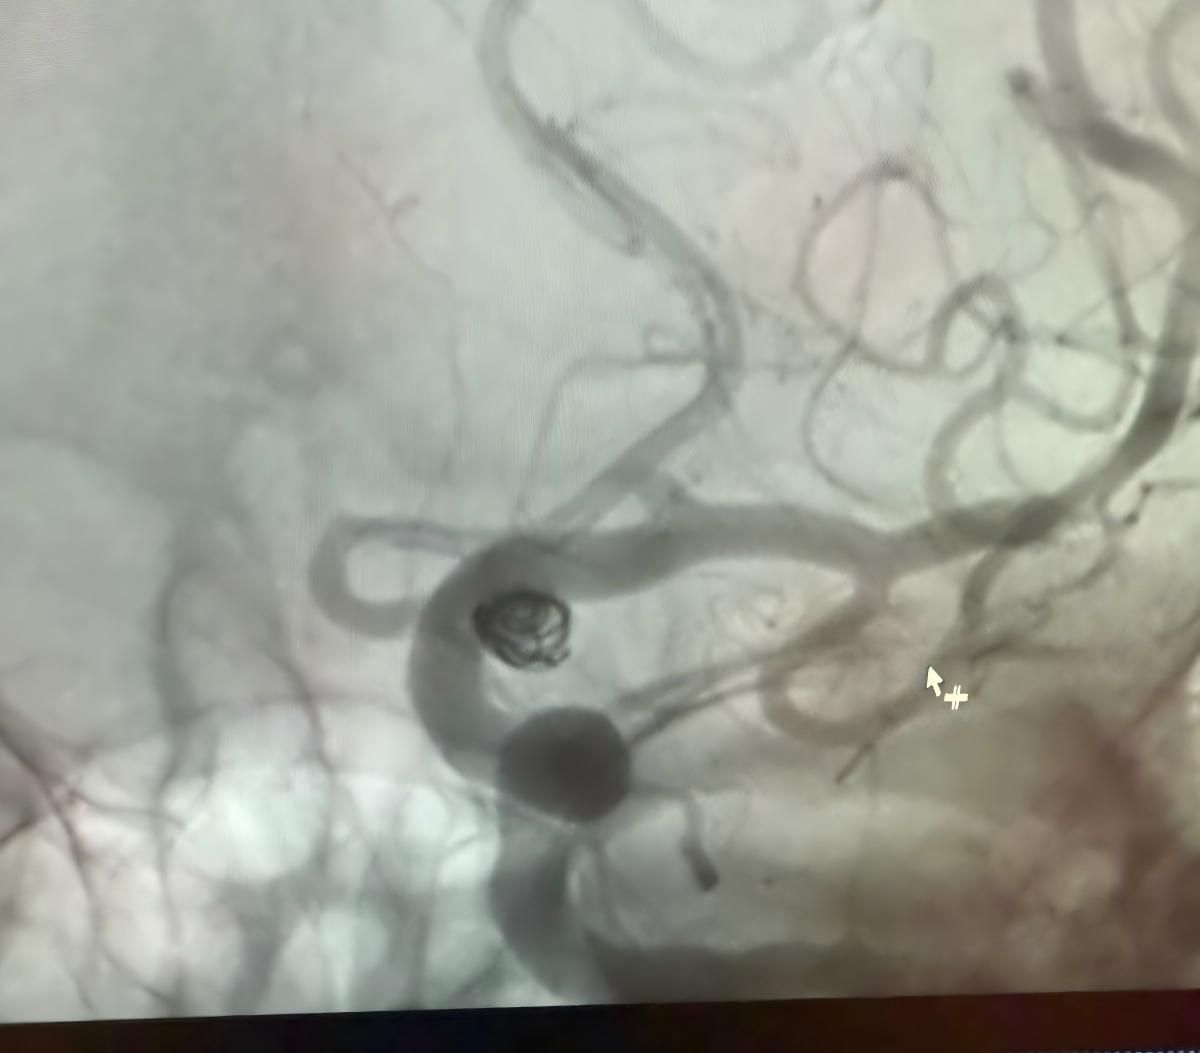

Dr. jorge mutis tarafından gerçekleştirilen clínica alma mater, medellín 'de son başarılı bir prosedürü paylaşmaktan memnuniyet duyuyoruz.

Tedavi nuva kullanıldı®Akış değiştirici (TJED-D 5.0-14), daha yoğun®3d bobin ve frepass®Posterior iletişim arter anevrizması için microcatheter (tjmc18 plus).

Dr. mutis, cihazın mükemmel görünürlüğünü vurguladı ve alınmanın pürüzsüz olduğunu kaydetti. Son sonuçtan büyük memnuniyeti dile getirdi.